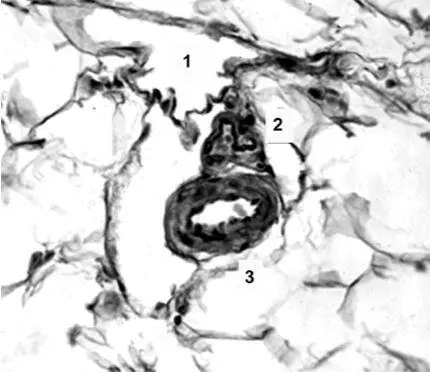

Микроциркуляторное русло в брыжейке тонкой кишки, гистологический срез: 1, 2 – лимфатические посткапилляры, проходящие в окружении сети соединительнотканных волокон и микрососудов; 3, 4 – пучок собирательной венулы и терминальной артериолы. Гематоксилин и пикрофуксин

Сосуды в брыжейке тонкой кишки, гистологический срез: 1 – клапан лимфатического посткапилляра; 2,3 – артериолы. Гематоксилин и пикрофуксин